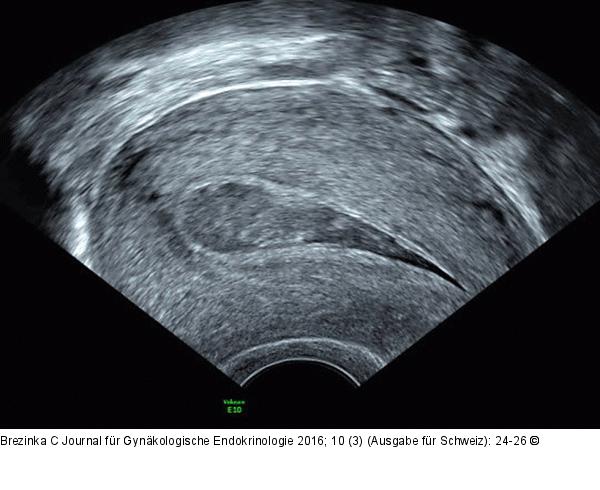

Abbildung 2: Ultraschall-Serometra Serometra unter IVF-Stimulation: Nach Fehldosierung bildete sich eine Ansammlung eher echodenser Flüssigkeit im Cavum uteri, sodass der Zyklus abgebrochen werden musste. |

Serometra unter IVF-Stimulation: Nach Fehldosierung bildete sich eine Ansammlung eher echodenser Flüssigkeit im Cavum uteri, sodass der Zyklus abgebrochen werden musste. |